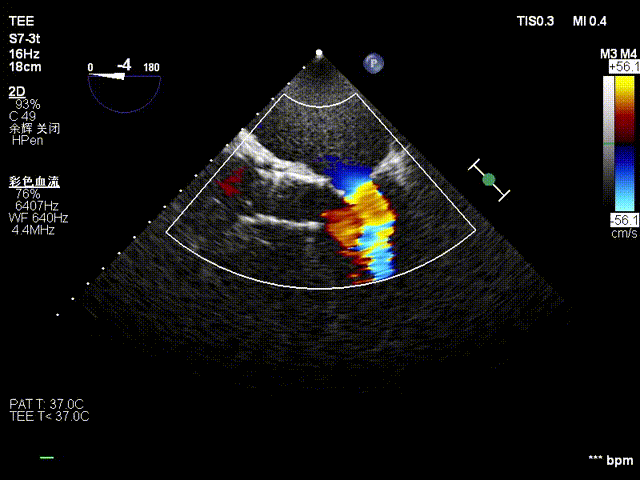

•超声检查:主动脉瓣上血流Vmax=5.35m/s,瓣口面积0.6~0.7cm²,主动脉瓣反流面积6cm²,EF值62%,诊断为“重度主动脉瓣狭窄,中量主动脉瓣反流”。

超声多切面评估,瓣膜植入位置理想,血流动力学改善明显